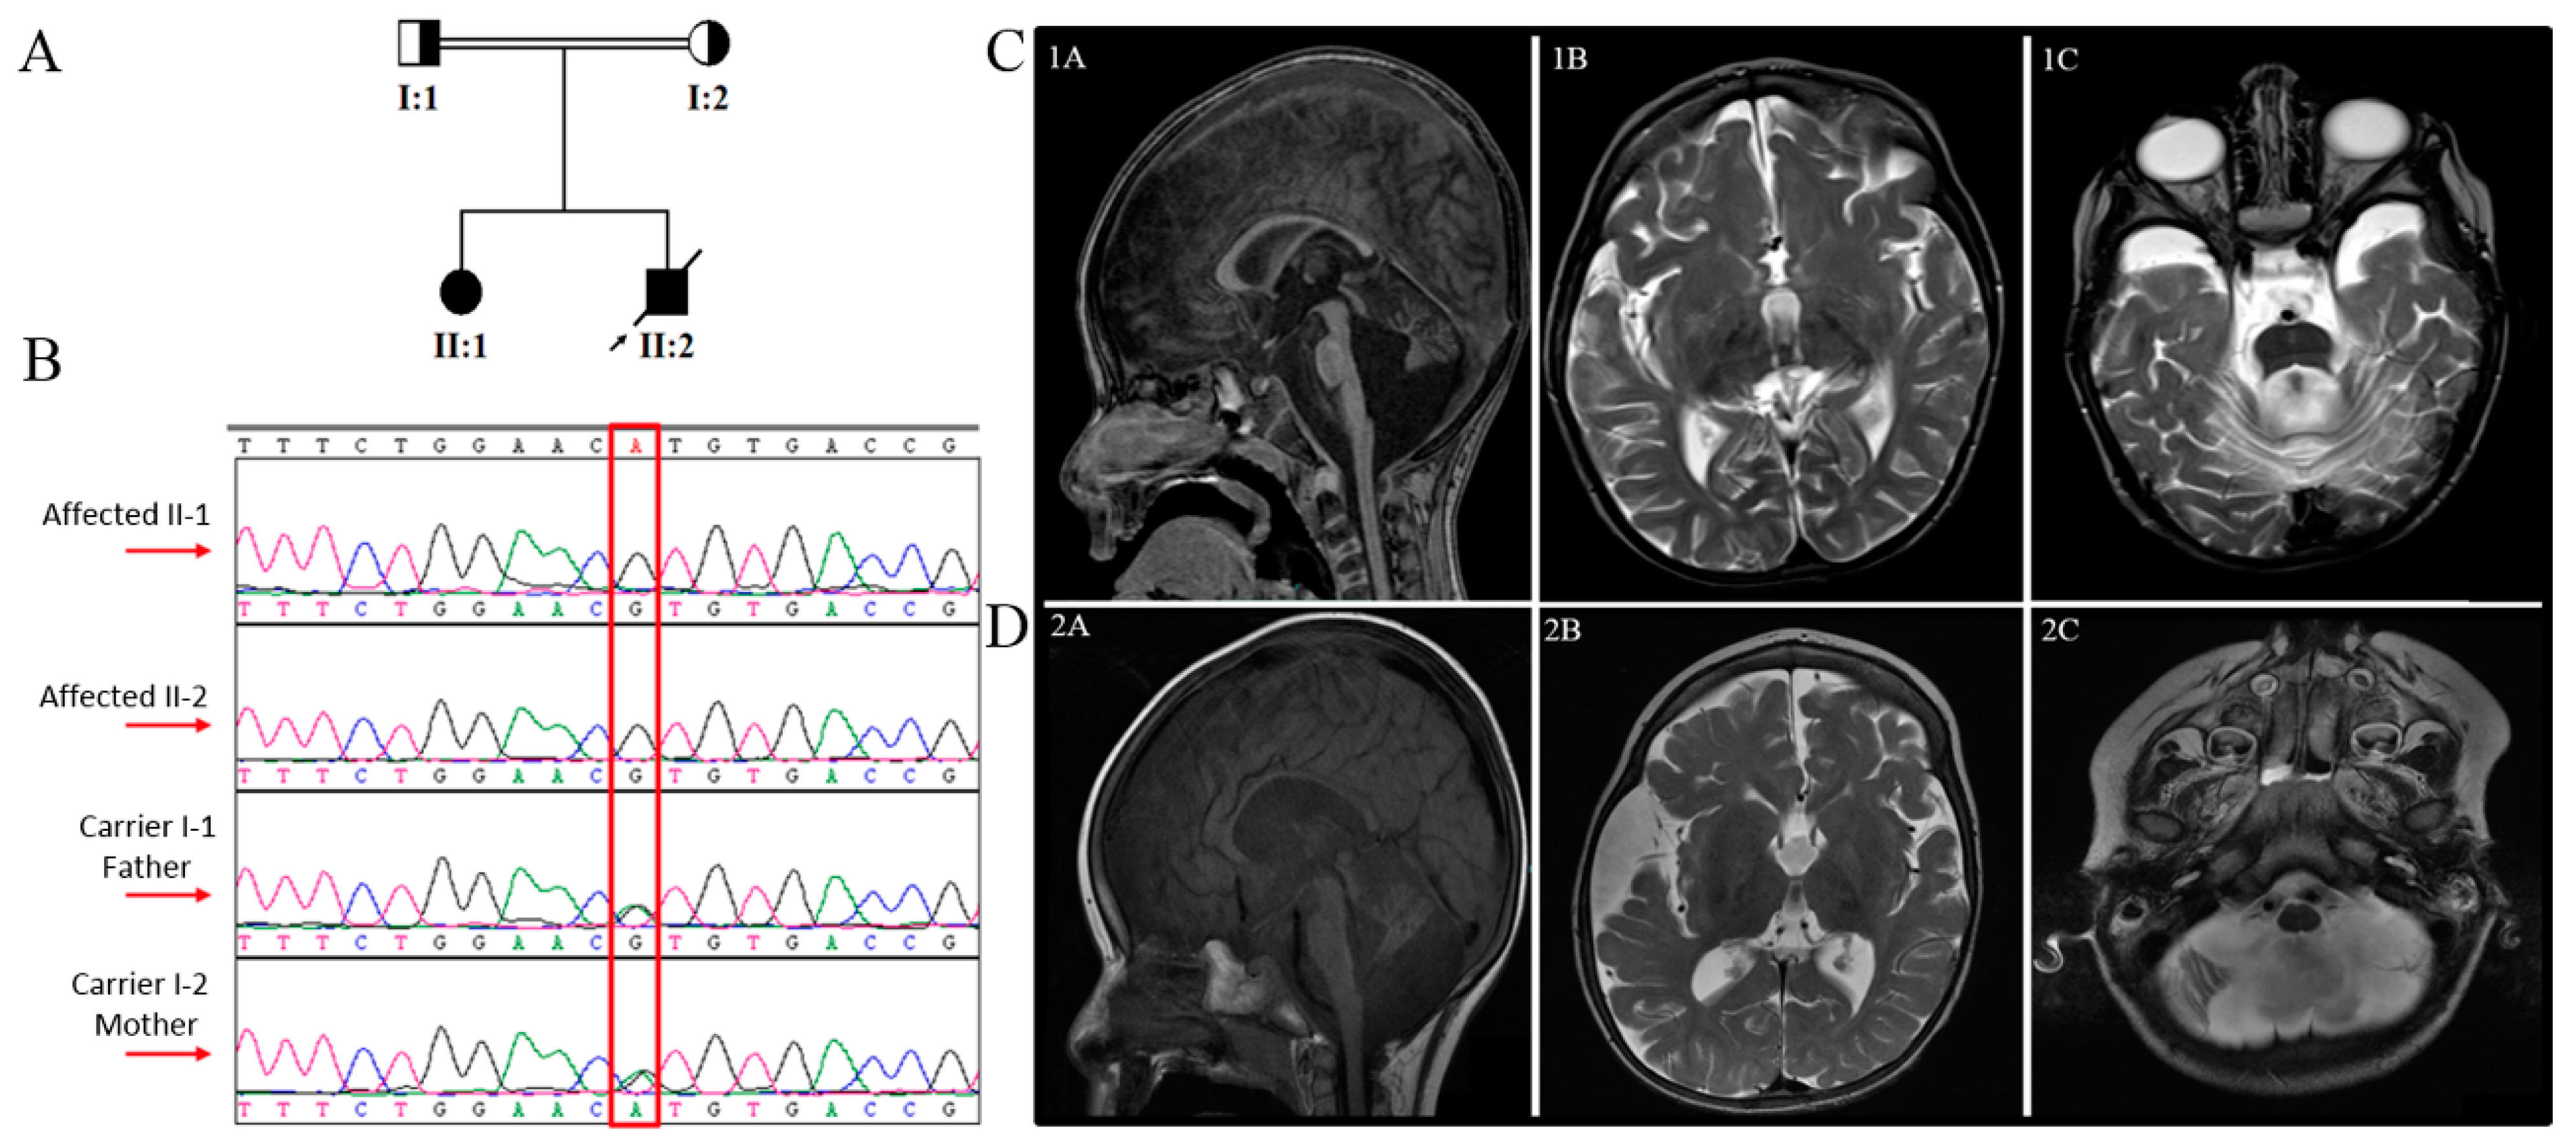

| MRI | Medulla, pons, cerebellar vermis, and both cerebellar hemispheres were rather small in size, with enlarged cistern magnum and the box-like appearance of the fourth ventricle. | Generalized atrophy, septum pellucidum was patent and vermian hypoplasia | Small atrophic cerebellum with prominence of the posterior fossa CSF spaces | NA | Bilateral symmetrical alteration of the signal intensity of the white matter of both cerebral hemispheres in the form of bright signal intensity on T2W and flair images, a picture probably reflecting disturbed myelination | Markedly prominent cortical sulci and subarachnoid cisterns were noted | Hypomyelination and callosal thinning |